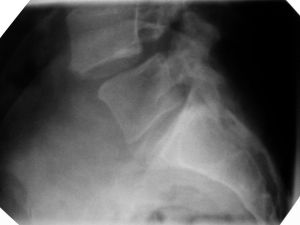

Wegweisend ist neben der klinischen Untersuchung die konventionelle Röntgenaufnahme der Lendenwirbelsäule in zwei Ebenen. Hier erkennt man einen Versatz zwischen den Wirbelkörpern. Eingeteilt wird die Spondylolisthesis in Grade nach Meyerding.

• Meyerding I°: Versatz der Wirbelkörper zueinander um weniger als 25 % der Wirbelkörpertiefe,

• Meyerding II°: Versatz um 25–50 %,

• Meyerding III°: Versatz um 50–75 %,

• Meyerding IV°: Versatz um mehr als 75 %.

• Spondyloptose: vollständig von vorne abgerutschter Wirbel